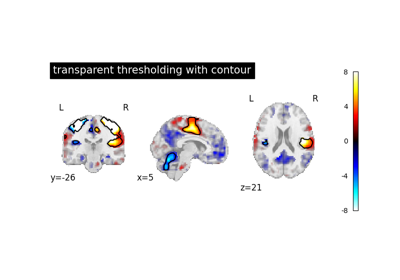

Examples using nilearn.datasets.fetch_spm_auditory¶

Intro to GLM Analysis: a single-run, single-subject fMRI dataset